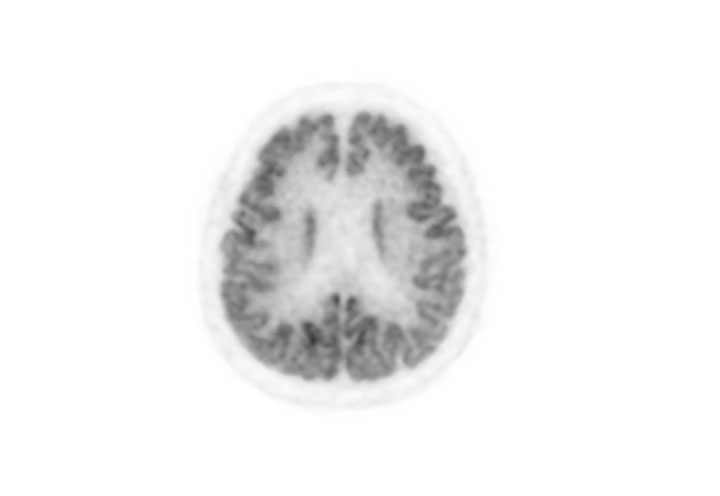

Head / Case3 : FDG

Axial

Courtesy : Kindai University Hospital

- Imaging protocol

- Injected dose: 4.49 MBq/kg, 18F-FDG

- Uptake time: 46 minutes

- Scan time: 30 minutes